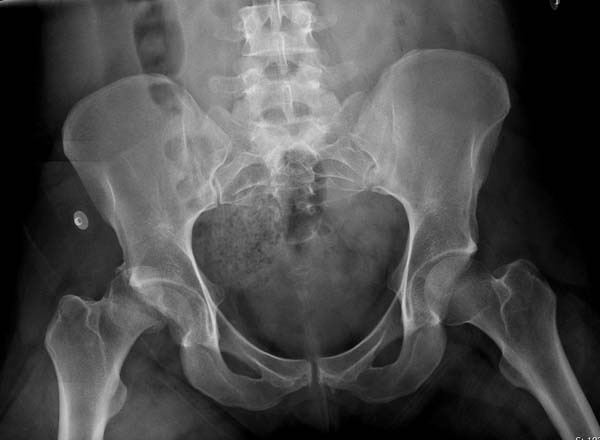

Здесь клинические примеры: Первый случай передний доступ, второй с ICP

monitor Flipp Trochanteris

и с переломом заднего края.